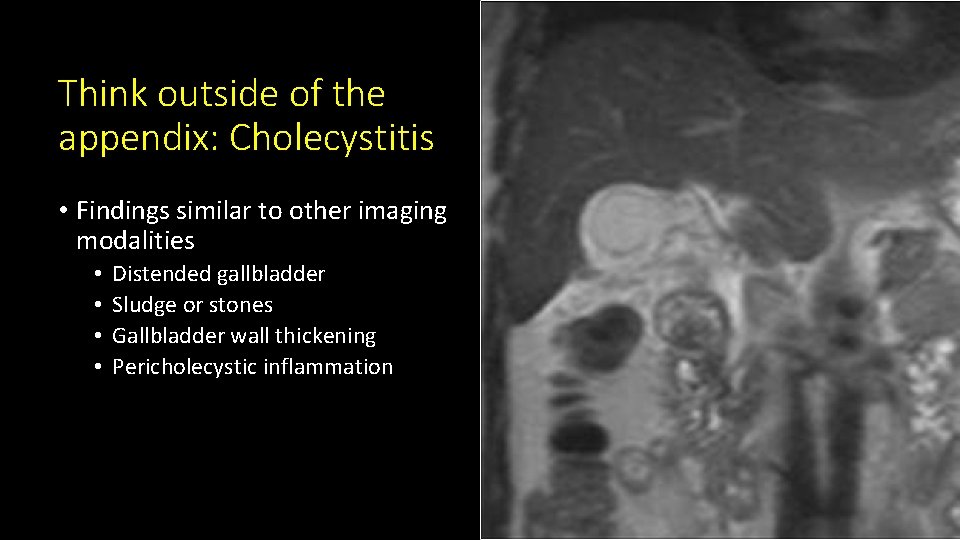

Think outside of the appendix: Cholecystitis • Findings similar to other imaging modalities • • Distended gallbladder Sludge or stones Gallbladder wall thickening Pericholecystic inflammation